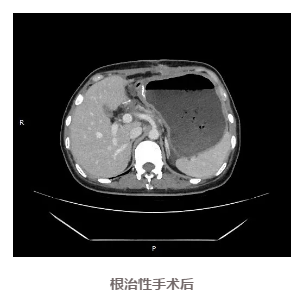

手术团队积极安排患者限期手术,先行腹腔镜探查发现,肿瘤与周围脏器无明显侵犯,可以手术切除,遂行开腹手术,最终成功进行了根治性切除。

患者恢复良好,术后8天顺利出院,目前定期来院复查,未发现复发迹象。